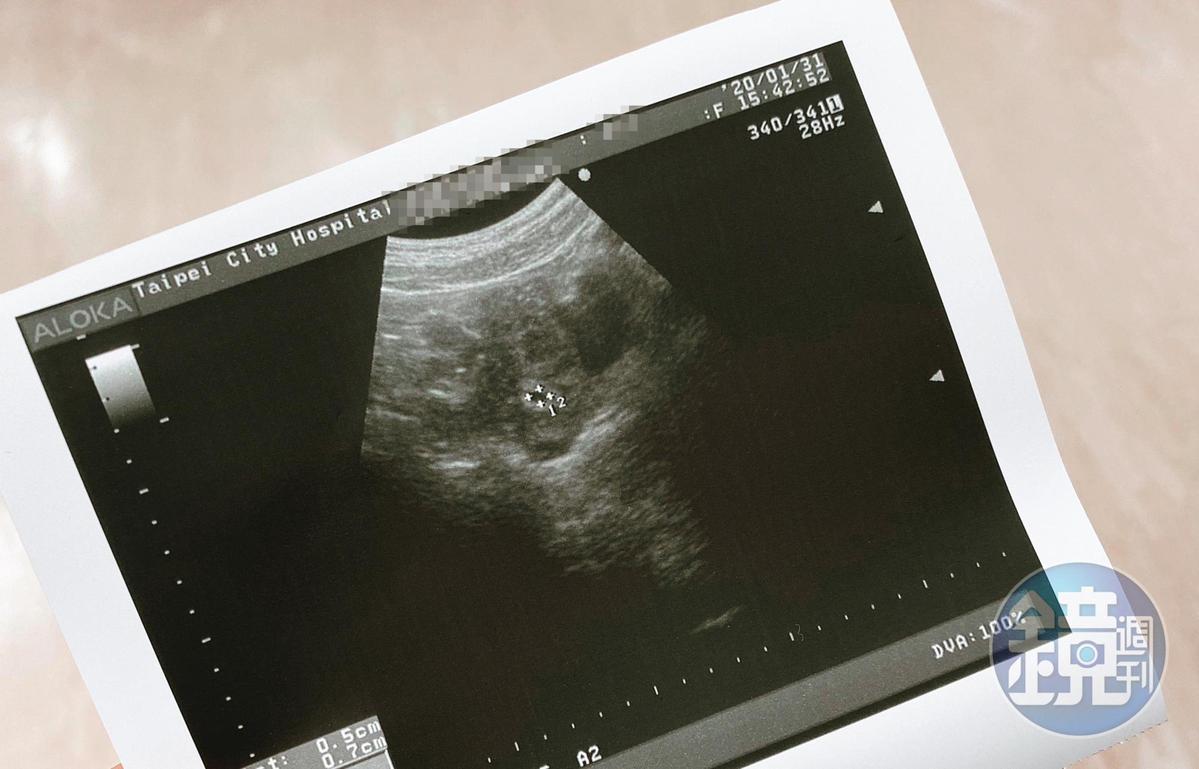

【渣男偷吃26女2】偽單身求婚挑鑽戒 超正外商女主管為他懷孕染性病